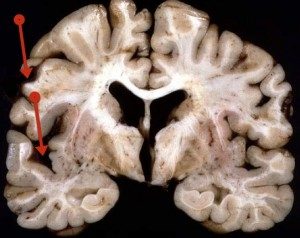

- Altersatrophie: Im Alter nehmen alle funktionalen (parenchymatösen) Zellen an Volumen ab, was insbesondere im Gehirn und Herz sehr ausgeprägt sein kann. Bei gleichzeitigem Vorhandensein von Lipofuszin spricht man wegen der bräunlicheren Farbe der Organe von der braunen Atrophie.

- Hirnatrophie